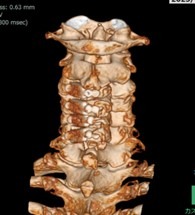

首で多い病気

• 変形性頚椎症

• 頚椎椎間板ヘルニア

• 頚椎症性脊髄症

• 頚椎後縦靭帯骨化症

首から手にかけての痛みやしびれ、手指の巧緻運動障害(細かい動作ができない)、歩行困難、膀胱直腸障害等の症状を伴う、上記のような病気があります。

• 頚椎椎弓形成術

適応となる疾患

頚椎症性脊髄症、頚椎後縦靭帯骨化症など

神経を圧迫している骨成分をチタン製のプレートを用いて挙上させることにより、狭くなった脊柱管を拡大させます。手術創もなるべく小さく当院では本手術を行っております。